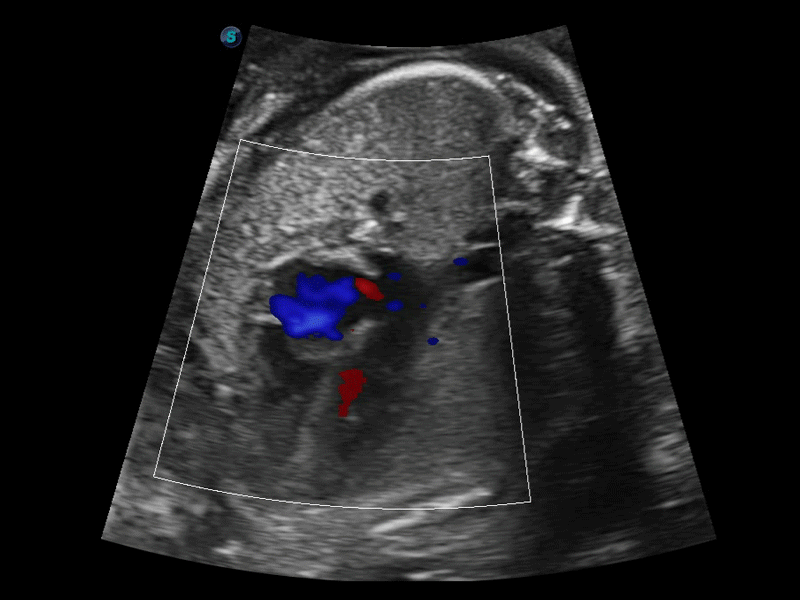

開立醫(yī)療通過不斷的技術(shù)創(chuàng)新,為大眾的生命健康提供持續(xù)關(guān)愛。P12 Plus采用全新一代超聲成像平臺,新平臺旨在將真實還原組織解剖結(jié)構(gòu)作為首要目標(biāo)。平臺采用全新集成化硬件模塊,搭載新一代芯片,系統(tǒng)性能得到大幅提升,為您的診斷提供了豐富的臨床信息。優(yōu)異的圖像表現(xiàn),豐富的探頭配置,全面的應(yīng)用功能,為您日常診斷提供了可靠的助手。

P12 Plus

彩色多普勒超聲診斷系統(tǒng)